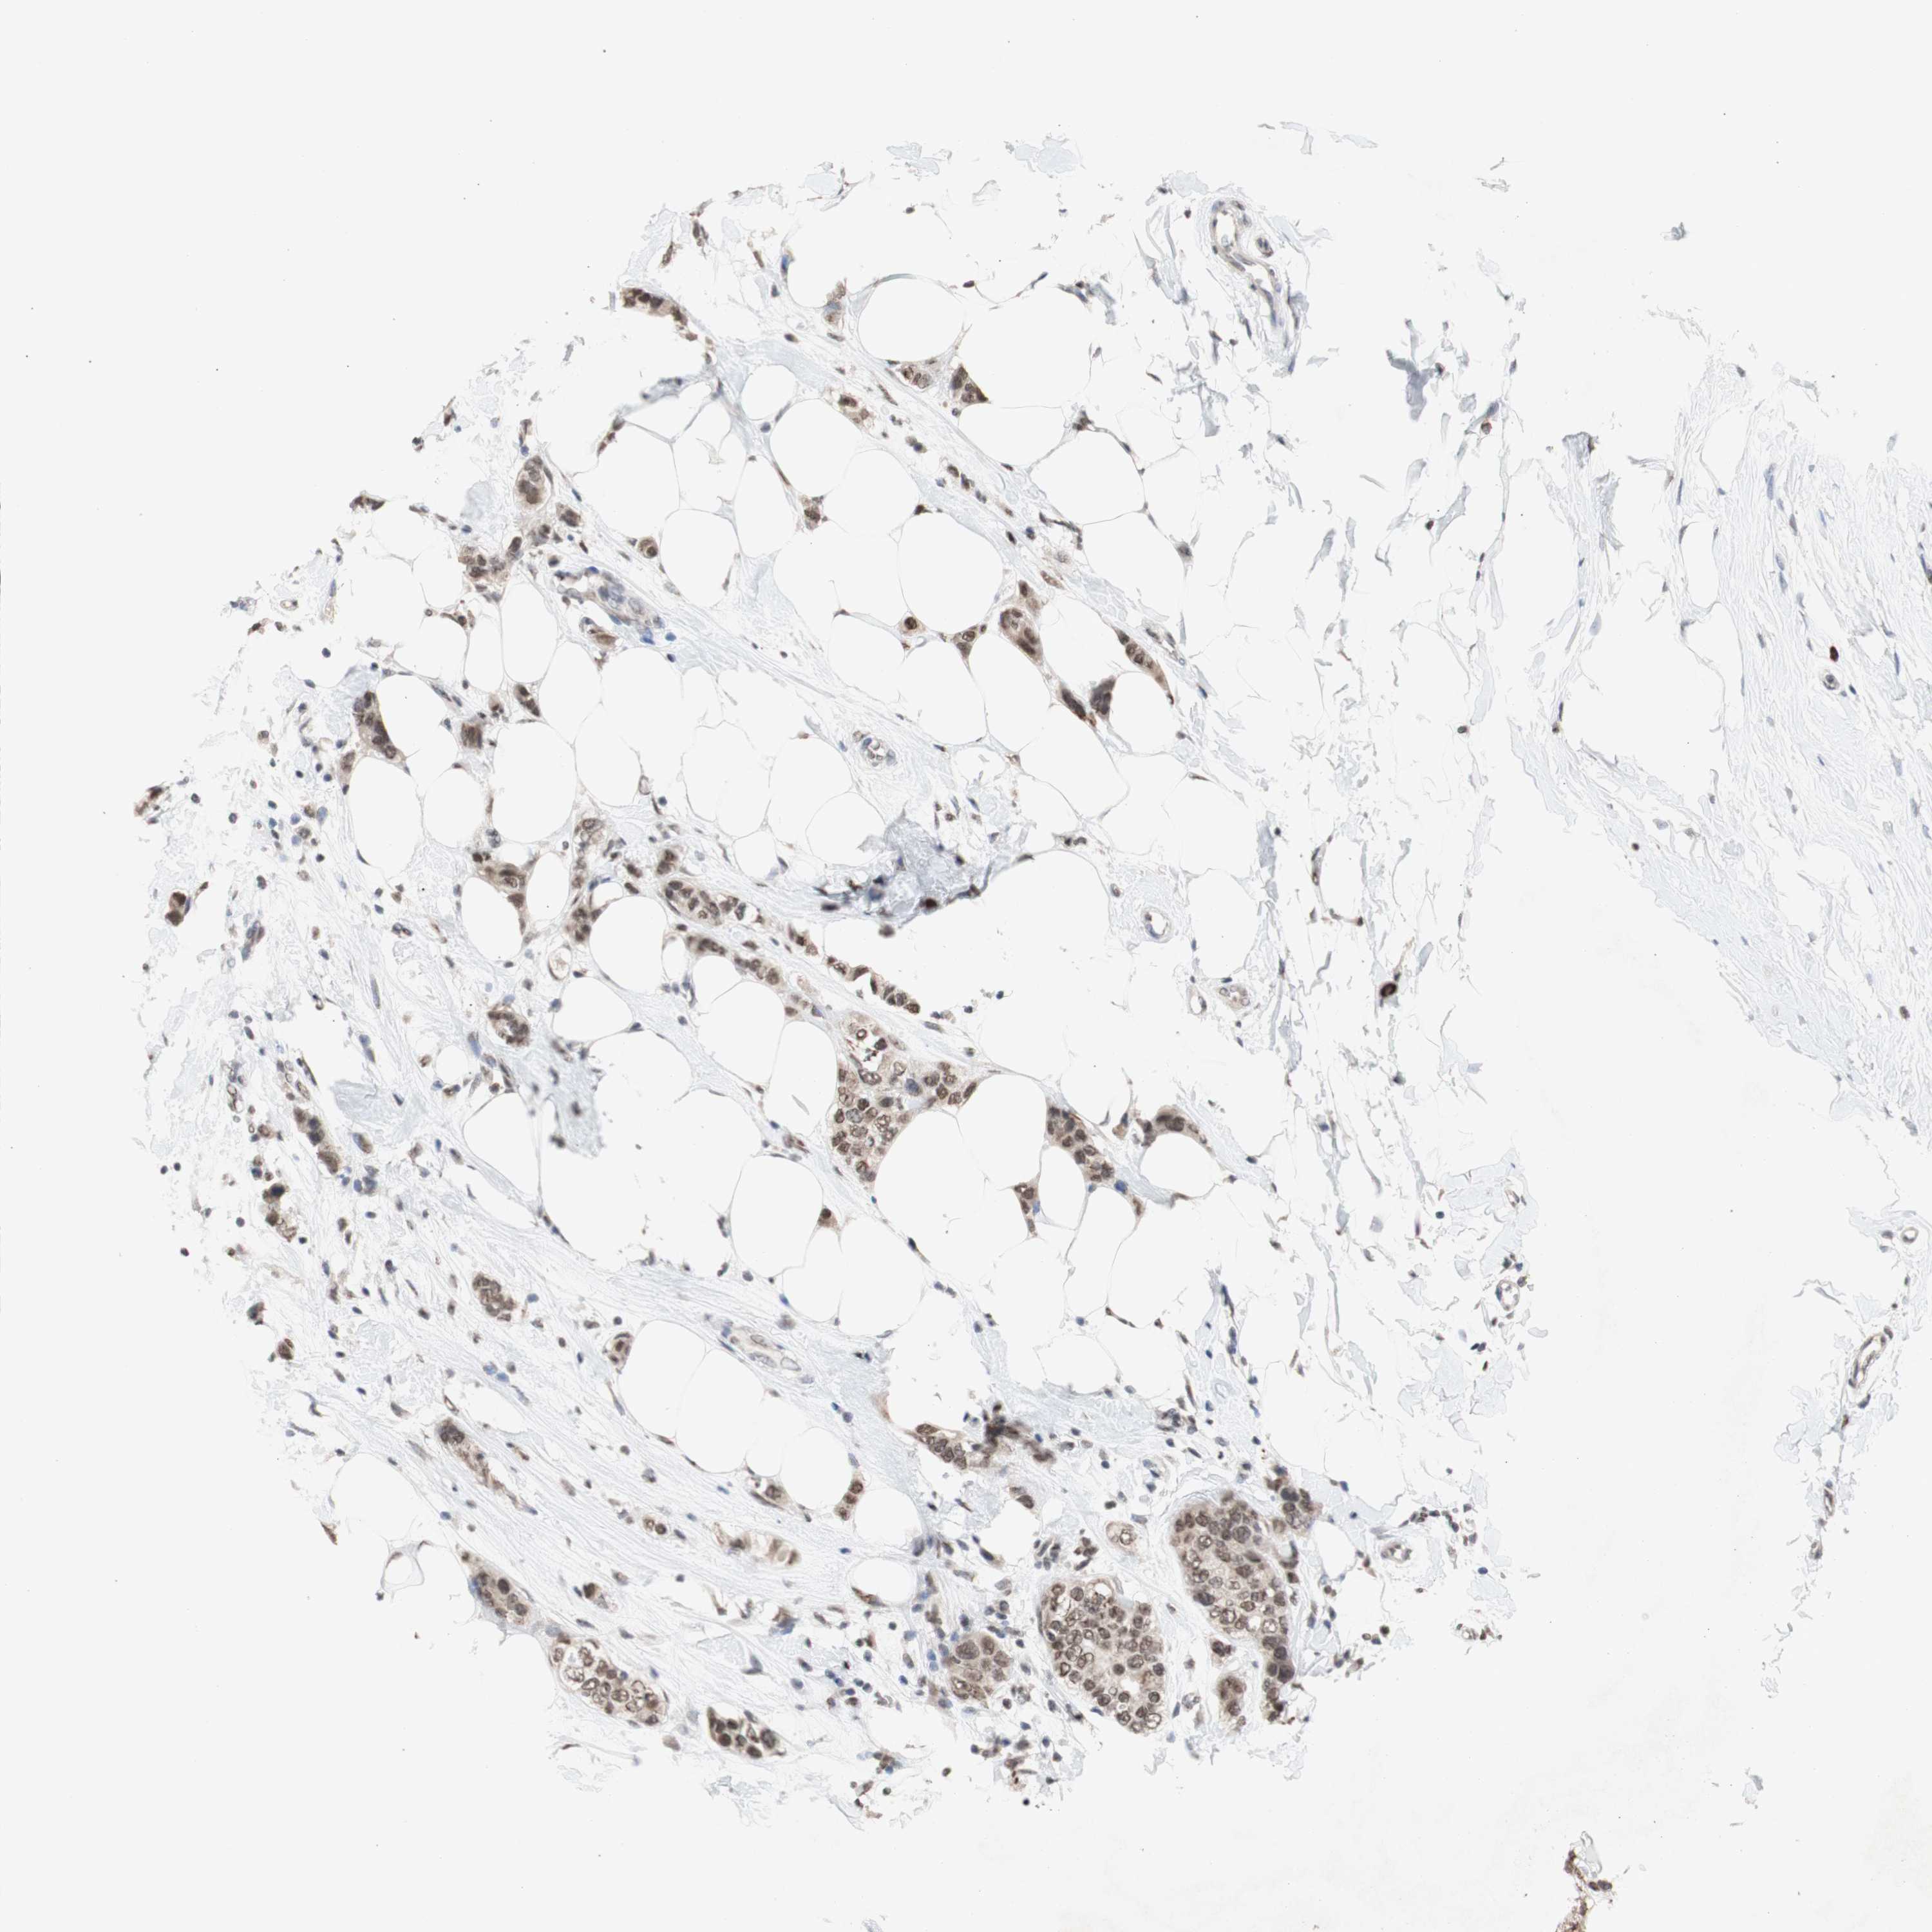

CANCER BREAST CANCER Show tissue menu

BRCA TCGA BRCA VALIDATION PROTEIN EXPRESSION

ANTIBODIES

AND

VALIDATION